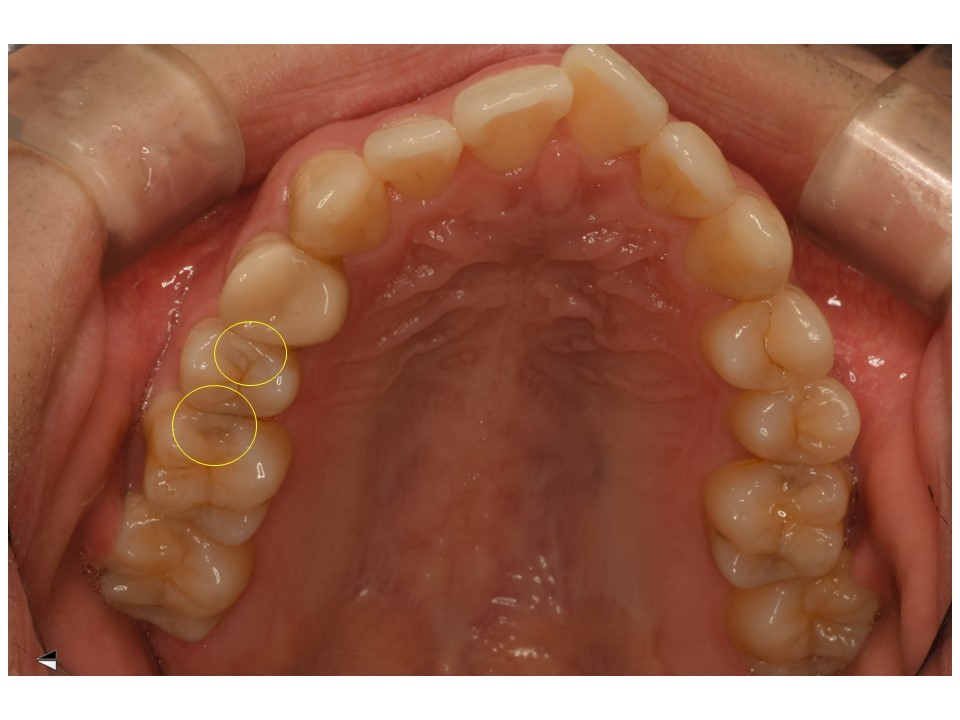

黄色の〇の場所にむし歯があります。

黄色〇のほかに、白い〇のところにもう蝕が確認されました。